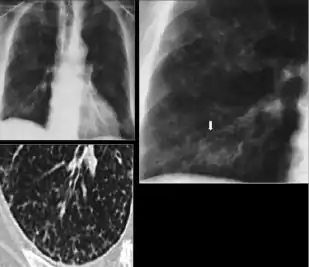

5. Other—Any other finding suggestive of prior TB, such as upper lobe bronchiectasis. Bronchiectasis is bronchial dilation with bronchial wall thickening.

Chest x-ray showing course bronchiectasis of the lungs post-primary pulmonary tuberculosis.